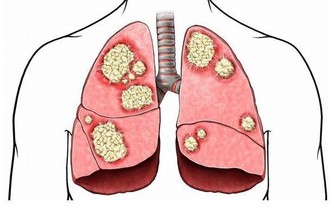

皮膚瘙癢、發黃:肝膽疾病

如果出現全身性的瘙癢,同時皮膚、眼睛、尿液等異常發黃,有可能是患上肝膽疾病的表現。